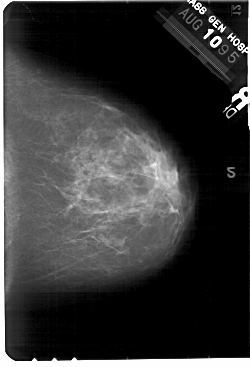

A_1445_1.RIGHT_CC

RIGHT_CC LINES 5491 PIXELS_PER_LINE 3736 BITS_PER_PIXEL 12 RESOLUTION 43.5 NON_OVERLAY